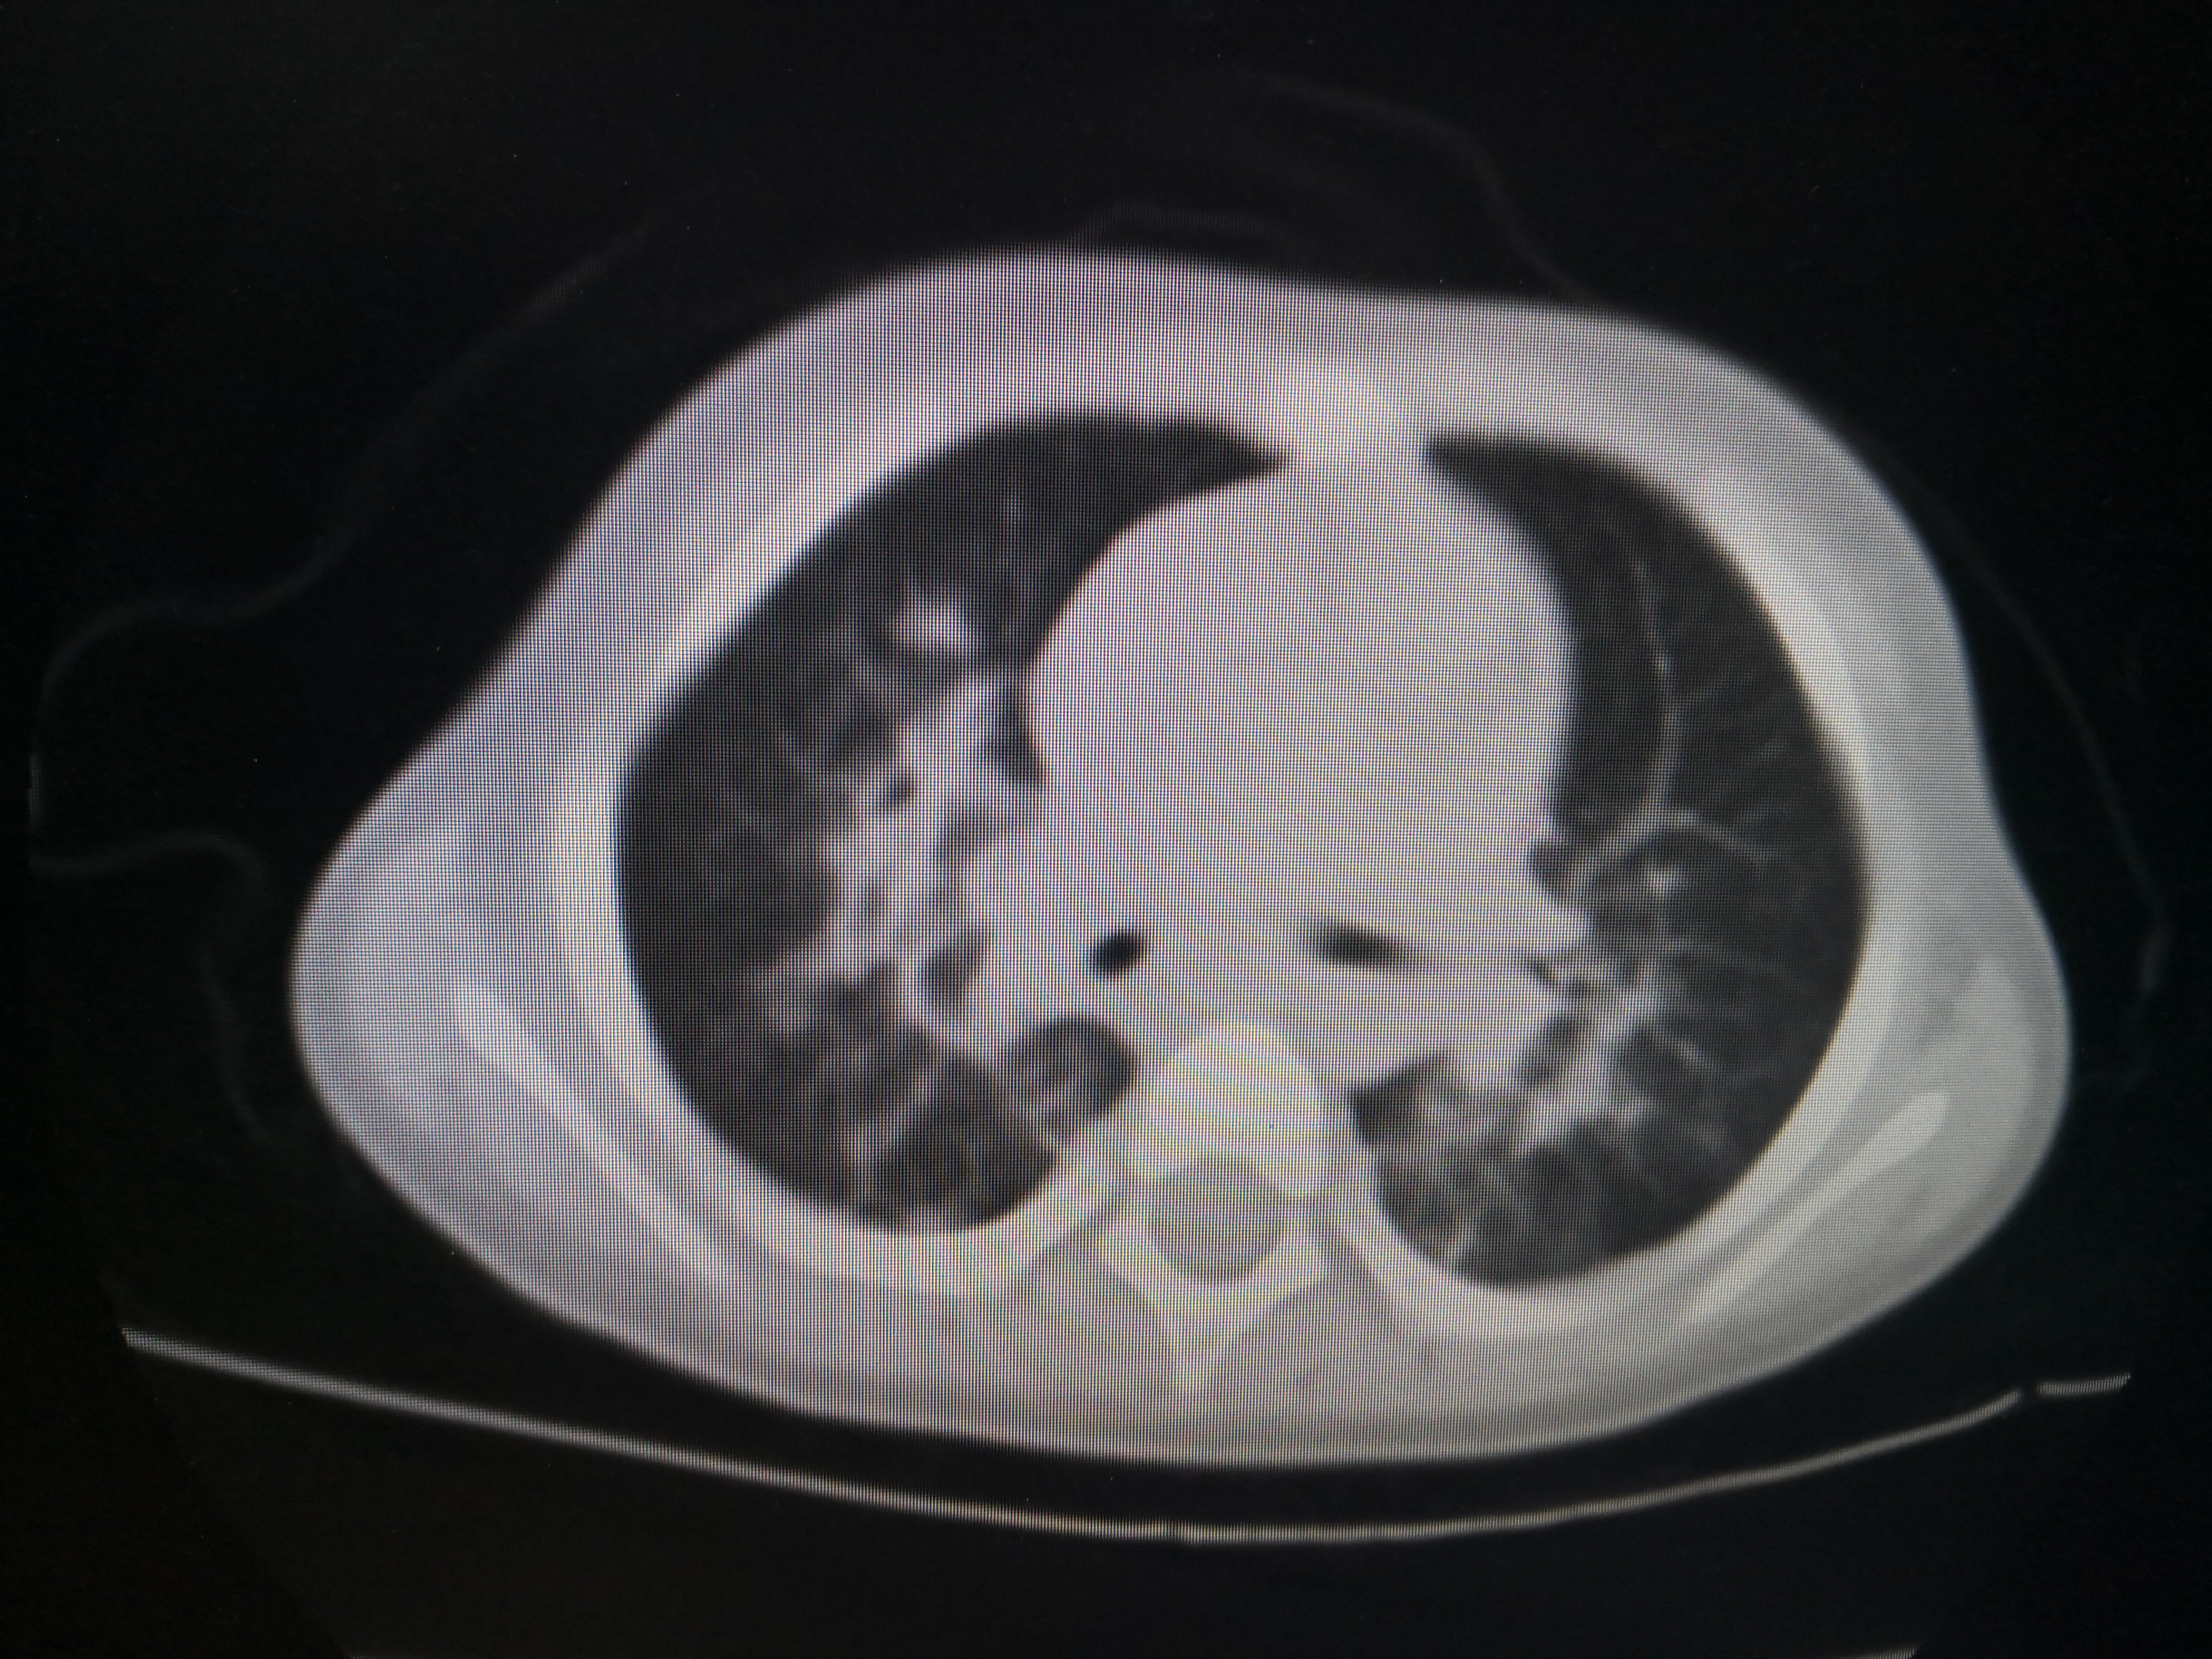

双肺炎症非常明显。CT结果出来后立即予以支气管镜灌洗治疗,在灌洗治疗过程中发现小朋友气管支气管里面大量黑色粪渣伴有较多黄色粪汁,遂将每个肺叶肺段灌洗干净,一周内完成2次支气管镜的灌洗治疗。第二次灌洗的时候双肺已经比较干净。出院后又口服了两周的强力抗生素。两周后复查胸部CT,结果如下

经过积极的救治,该小朋友双肺基本完全恢复正常。值得庆幸的是未留下任何肺部及大脑等重要脏器的后遗症。在这个小朋友的治疗过程中非常重要的治疗措施就是积极的予以支气管镜的灌洗治疗,及时清除了肺及气管支气管内的粪渣及粪汁,才能使得小朋友顺利康复!